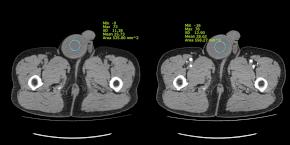

• A large low echoic mass in Rt scrotum and non-visualization of normal Rt testis

• Homogeneous low attenuated non-enhancing Rt testicular mass on CT